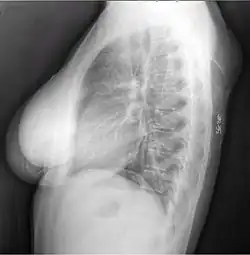

Diffuse lipomas of the neck and abdomen -

Benign symmetric lipomatosis (Madelung disease) is another condition involving lipomatosis. It nearly always appears in middle-aged males after many years of alcoholism, but nonalcoholic males and females can also be affected.[21]